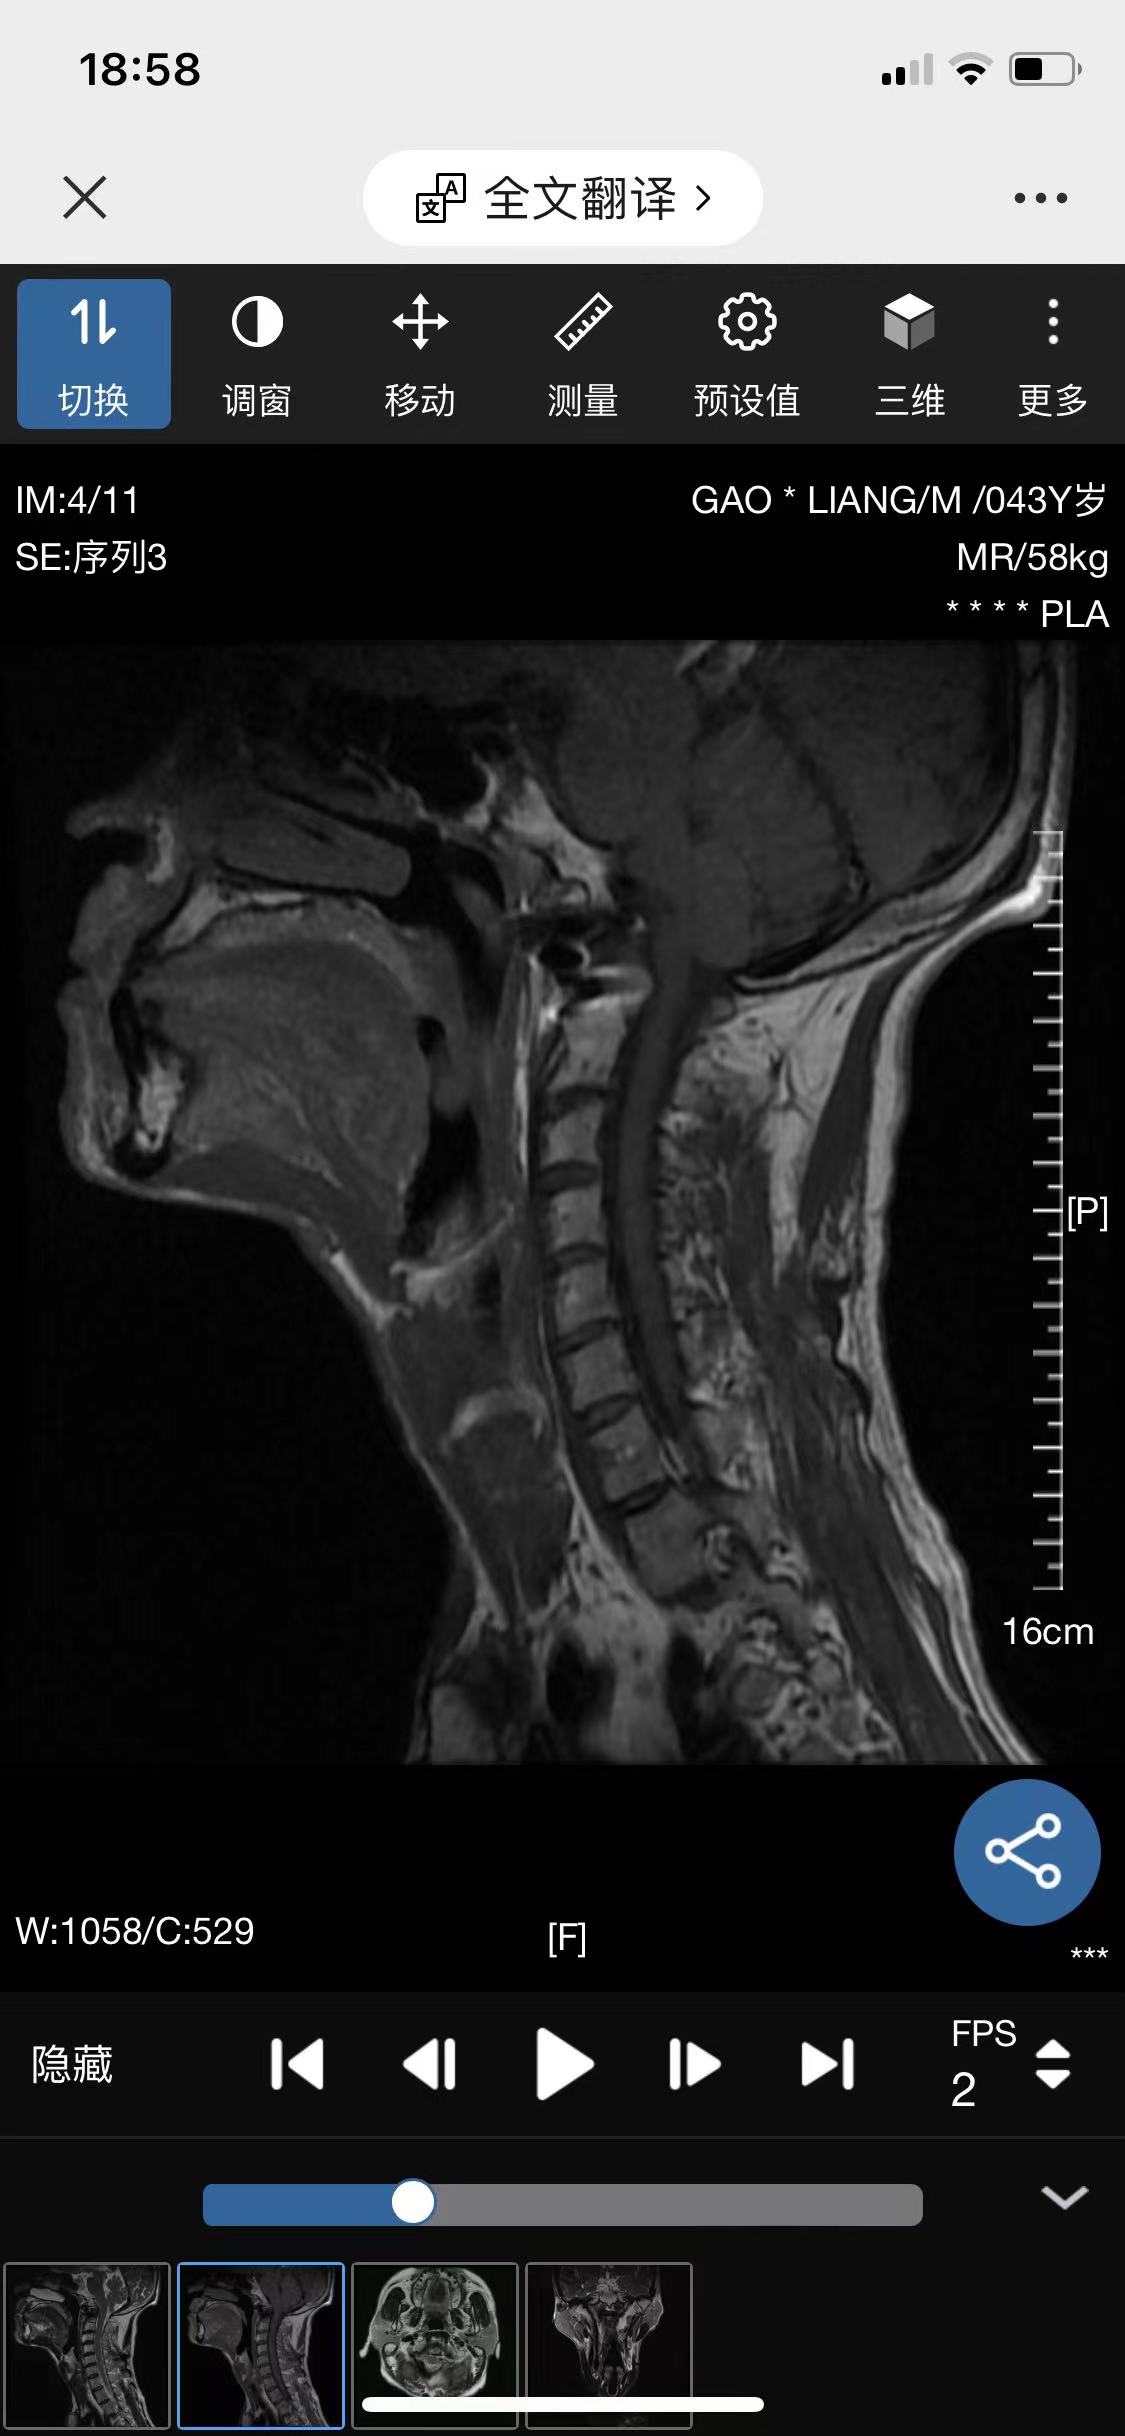

• 诊断:寰枢椎脱位

• 影像: